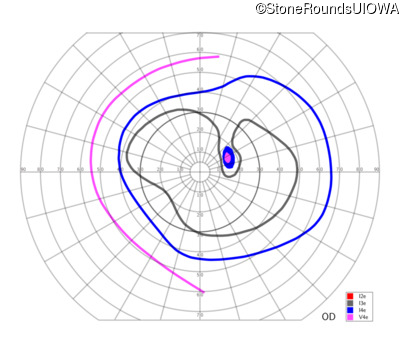

This 52 year old man had normal vision until his mid 30's when he began to have trouble distinguishing colors. the issuing 10 years he had a gradual loss of visual acuity accompanied by increasing photophobia.

| Age at visit: 55 years |

| Age at visit: 58 years |

| Age at visit: 61 years |

| Age at visit: 64 years |